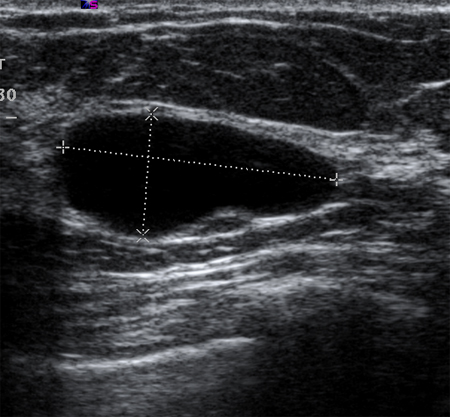

Simple cysts are smooth, round, well-demarcated, fluid-filled lesions, and are anechoic. If they have no internal septations or debris, they may simply be followed. Ultrasound is not able to detect microcalcifications in the breast.[Figure caption and citation for the preceding image starts]: Ultrasonographic image of a simple cystCourtesy of Dr Lane Roland, University of Louisville; used with permission [Citation ends].